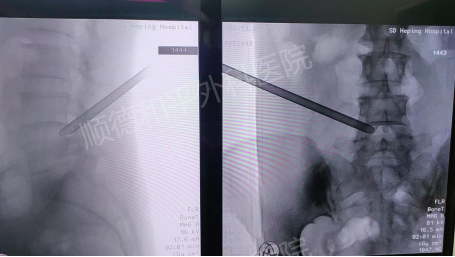

结合李女士的病情,张哉炯主任团队经过详细评估,为其制定了精准的治疗方案——微创经皮后路椎间孔镜下L4/5椎间盘髓核射频摘除术。

该术式是一种先进的微创手术,具有创伤小、恢复快等优势。手术通过椎间孔镜,在高清视野下精准定位突出的髓核组织,利用射频技术将其摘除,从而解除对神经的压迫,缓解疼痛麻木等症状。

李女士的手术历时2小时,过程顺利。术后当天,她的左下肢放射性麻木疼痛便明显缓解,腰部伤口仅有轻度疼痛,夜间睡眠正常。术后第1天,左下肢轻度胀痛较前显著减轻,已能自如卧床翻身活动,且无下肢麻木及乏力等不适。